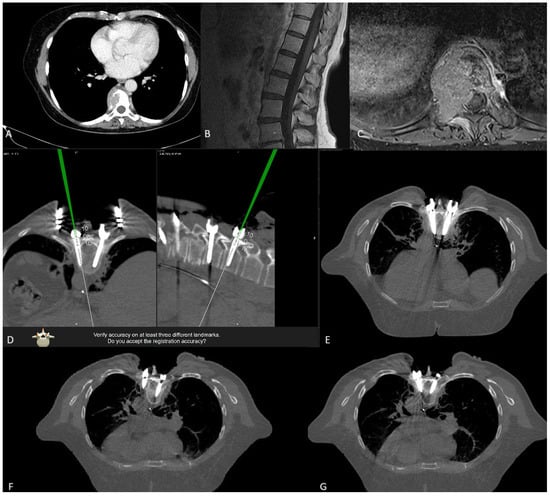

After exposing the bone anatomy and fixing the reference array, a registration scan with automatic registration of the patient was performed. The surgical area is covered with a sterile drape so that the reference array is visible to the navigation camera, and the scan length is marked with a sterile pen. The registration scan is performed during apnea so that any respiratory artifacts that may occur do not affect accuracy. The scan takes 7–12 s. All personnel leave the operative room for the scan, so that the radiation exposure for staff is zero. Low-dose protocols were used for the scans. The effective dose is calculated by multiplying the total dose length product (DLP) by ED/DLP conversion factors (17.8 μSv/Gy × cm for thoracic and 19.8 μSv/Gy × cm for lumbar spine scans). After the scan, the image data was automatically transferred to the navigation system (BrainLab, Munich, Germany) without user interaction for automatic patient registration. The entire process of covering the patient with a sterile drape for the scan, as well as the scan itself, takes 10–15 min. The registration accuracy was checked and recorded using a pointer and skin fiducials and by placing the pointer in the fixation area of the registration array. In open cases, additional verification of the bony structures was performed. (Figure 5 and Figure 6).

After selecting a region of interest (ROI), the iCT scan was merged with a preoperative scan. A rigid fusion was performed, and in cases of instability of the spine due to a tumor or fracture, as well as in cases of longer constructs, elastic fusion was performed (Figure 7 and Figure 8). In selected cases with longer thoracolumbosacral constructs, two scans were performed, with repositioning of the reference array to avoid compromising accuracy for levels far from the reference array. After fusion of the scans, the planned screw trajectories were checked and corrected as necessary (Figure 9) [4].

3.10.3. Case 3

An 81-year-old patient with spondylodiscitis, intraspinal empyema at L2-S1, and an L4 fracture underwent decompression for empyema evacuation and RG PS placement at L2-S1, followed by cage implantation (Figure 22, Figure 23 and Figure 24).